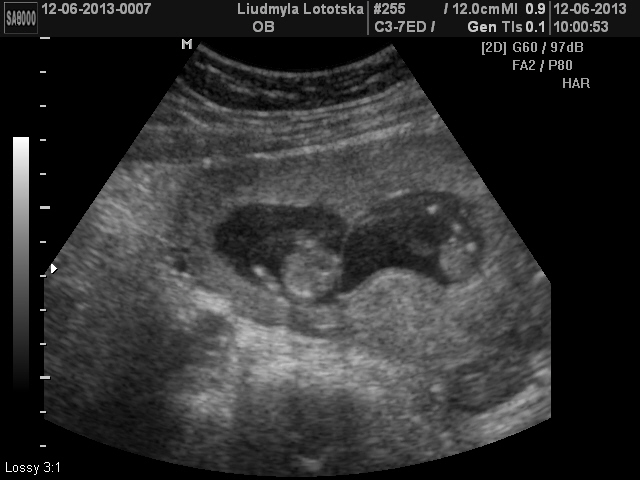

Зашли в кабинет,я легла,муж сел рядом. Когда узистка приклала только датчик наши сокровеща лежала один к одному попами)))потом когда начали все измерять и я увидила как они там пинаються и ручками машут меня поперло- слезы радости было не удержать...на мужа я вообще не смотрела))...Одного малыша хорошо померяли,а вот второй!!!....ух))))....кувыркался и не давал себя посмотреть)Но все таки все получилось,чему мы были очень рады)))....Кстати вот на этого хулигана сказали что будет мальчик!))

Ну и покажемся вам,мои дорогие: